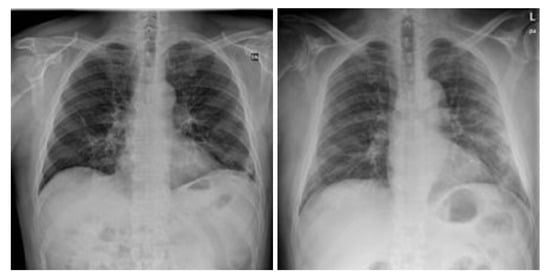

3.4.1. NIH Dataset

3.4.2. COVID-19 Image Data Collection

3.4.3. COVID-19 Radiography

3.4.4. BIMCV COVID19+

3.4.5. Montfort Dataset